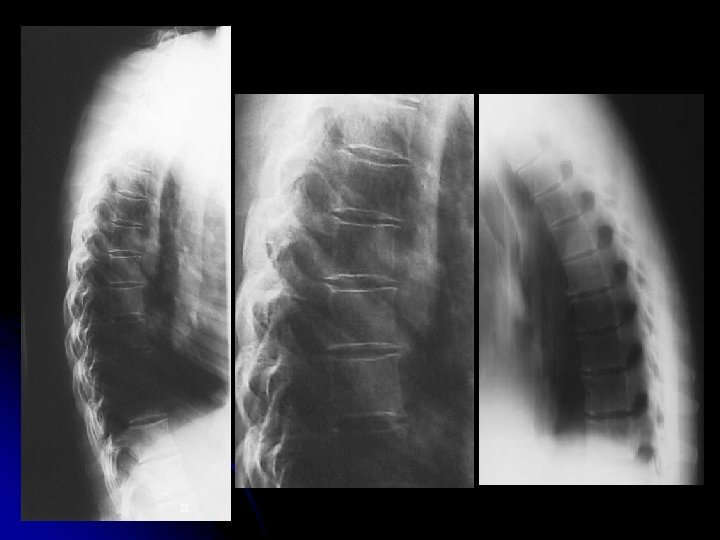

Rachis dorsal de profil Position: debout, de profil strict, Epaules et bras dégagés en avant. centrage pointe de l'omoplate, 4 doigts en avant des épineuses ; Réaliser le cliché en cours de respiration.

l Résultats : l courbure physiologique l morphologie et structure des corps vertébraux. l Hauteur des espaces inter-vertébraux. l Morphologie des arcs postérieurs